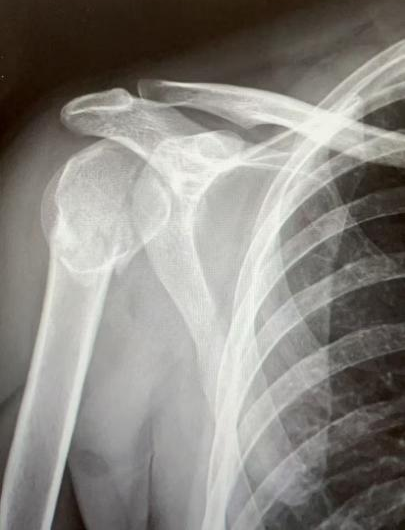

10月5日,40岁李先生摔倒致右肩部着地,8:40入院后,高峰医师团队诊断为“右肱骨近端粉碎性骨折”,13:35做好充分术前准备后历经3小时手术完成。

图片